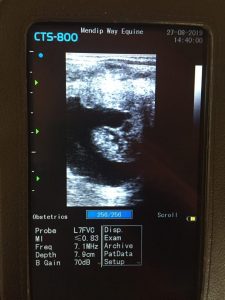

The CTS-800 is equipped with a bright seven-inch LCD monitor that delivers sharp, readable imaging across B, 2B, Zoom B, B/M and M modes. A standout feature is the integrated gravity sensor, which automatically flips your image vertically or horizontally based on how you are holding the unit. It is a small detail that makes a real difference when you are working in tight or awkward positions, which anyone experienced in large animal practice will immediately appreciate.